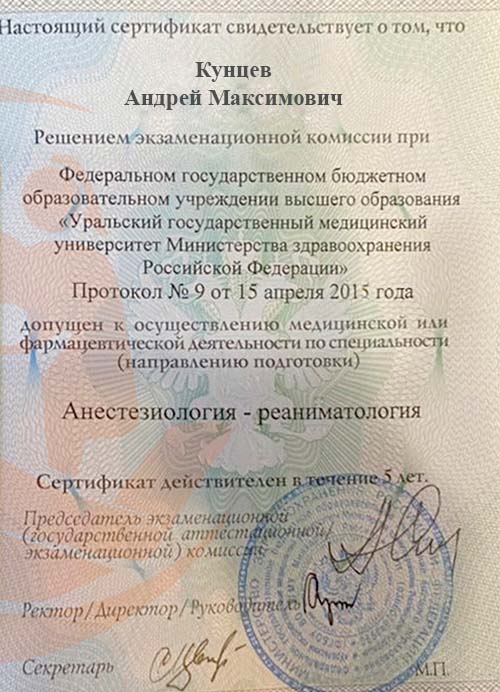

- 2015 - Уральский государственный медицинский университет (Повышение квалификации - анестезиология и реаниматология);

Андрей Максимович Кунцев — высококвалифицированный анестезиолог-реаниматолог с более чем 12-летним стажем работы в сфере оказания специализированной медицинской помощи. Обладает первой категорией и глубокими знаниями современных методов анестезии и реанимации, которые применяет для обеспечения безопасности пациентов во время различных хирургических и терапевтических процедур.

Андрей Максимович окончил Уральский государственный медицинский университет в 2009 году по специальности «лечебное дело». Уже через два года он успешно завершил ординатуру по анестезиологии и реаниматологии в том же университете, что дало ему необходимую специализацию для работы в области интенсивной терапии и обезболивания. В 2015 и 2020 годах прошёл курсы повышения квалификации по анестезиологии и реаниматологии, что подтверждает его стремление оставаться в курсе новейших методик и практик в своей области.